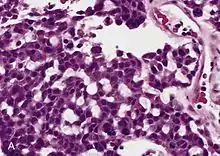

Adrenal tumors are often not biopsied prior to surgery, so diagnosis is confirmed on examination of the surgical specimen by a pathologist. Grossly, ACCs are often large, with a tan-yellow cut surface, and areas of hemorrhage and necrosis. On microscopic examination, the tumor usually displays sheets of atypical cells with some resemblance to the cells of the normal adrenal cortex. The presence of invasion and mitotic activity help differentiate small cancers from adrenocortical adenomas.[6] Several relatively rare variants of ACC include: